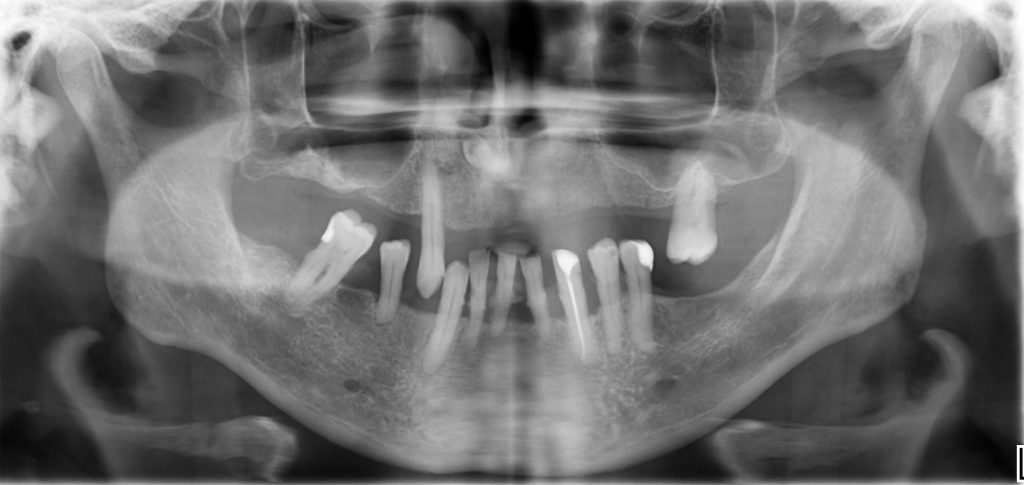

95Пациент 65 лет обратился за комплексной стоматологической реабилитацией с жалобами на отсутствие зубов и эстетическую неудовлетворенность. Пациент долгое время не обращался за стоматологической помощью, вследствие чего были утеряны зубы на верхней и нижней челюсти. В полости рта наблюдаются пародонтальных патологии имеющихся зубов, зубоальвеолярное изменение в виде феномена Попова – Годона (рис 1,2,3.) На панорамной рентгенограмме […]